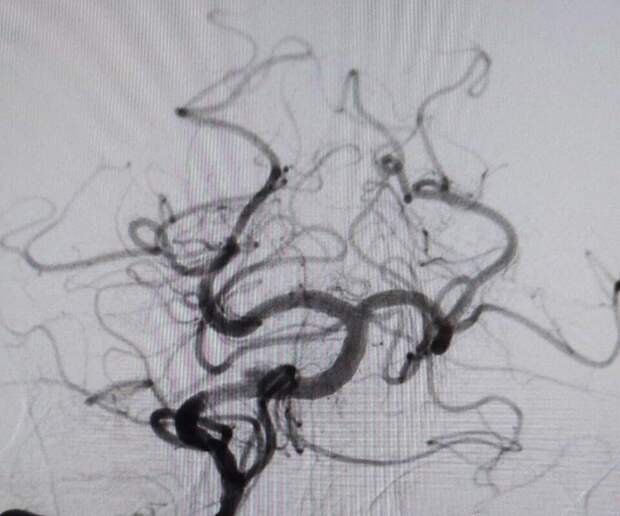

Прибывшая на вызов скорая приняла решение о госпитализации."В ходе обследования врачи диагностировали закупорку основной артерии, обеспечивающий кровоснабжение важнейших отделов головного мозга. Это очень тяжелое состояние с крайне высокой летальностью", - пояснили врачи.

Мужчине провели экстренную операцию, в ходе которой удалили тромб и установили стент.